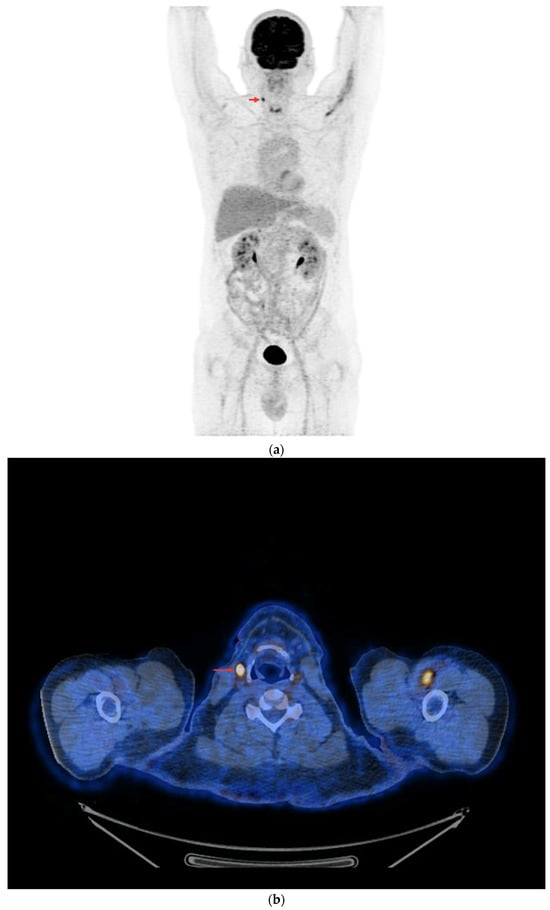

- In the case of non-resectable lesions (due to a lack of the patient’s consent to repeated surgery, lack of technical possibilities of surgery or other reasons), the lesions were verified using FNA only, and after verification, the patients remained in the observation group or were referred to tyrosine kinase inhibitor (TKI) therapy (Figure 4a,b).

Figure 4. PET/CT with [18F]FDG (a) Maximum-intensity projection (MIP). (b) Axial fusion projection. These show an example of accumulation of the [18F]FDG in the left retroesophageal lymph node (red arrow). The lesion was verified as being metastasized DTC using FNA. Due to comorbidities and the patient’s lack of consent, resection of the lesion was abandoned; the patient was left in the observation group, with a stable Tg concentration in follow-up determinations (maximum natTg concentration 3.91 ng/mL, maximum sTg concentration 19.62 ng/mL).